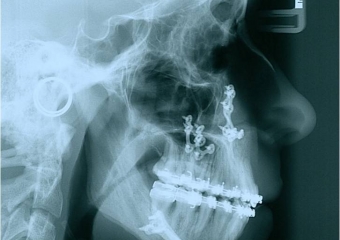

Telerradiografia de perfil após a cirurgia - Clínica Cliniface

Telerradiografia de perfil após a cirurgia